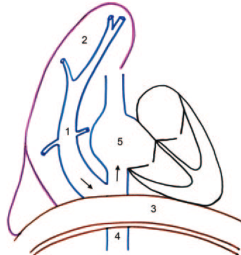

Tetralogie de Fallot

- Horizontalisation du Coeur (du à l’hypertrophie pulm)

- Signe du Coeur en Sabot (apex surelevé)

- Non visibilité du tronc pulmonaire

- Tetralogie:

- CIV

- Aorte à cheval

- Sténose et hypoplasie de l’infundibulum pulmonaire

- Hypertrophie du VD

- Si CIA associée = Pentalogie de fallot

- 1/4 des Fallots ont un arc aortique droit sans cardiomégalie ni vasculature pulmonaire augmentée (contrairement au TAC)